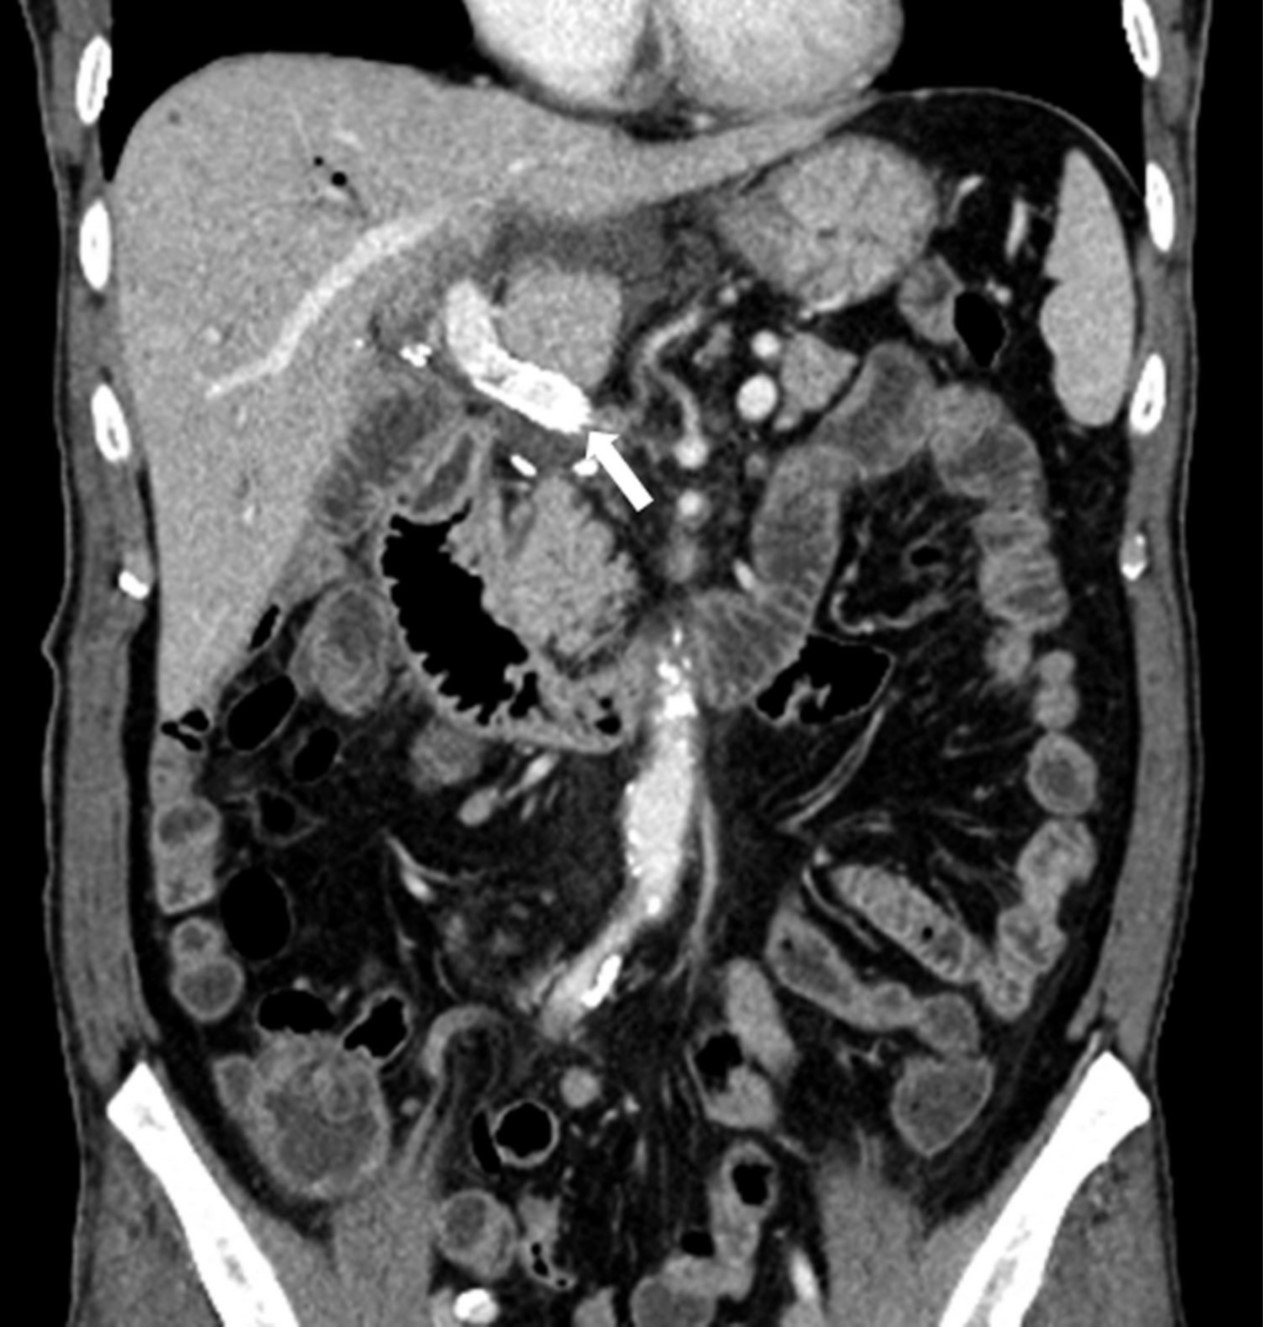

초음파 유도하에 간우엽 S6 담관을 천자하여 5Fr sheath(Terumo, Tokyo, Japan)를 삽입하고 5Fr KMP catheter(Cook, Bloomington, IN, USA)를 상장간막정맥에 위치시키고 시행한 직접 문맥조영술에서 주문맥에 부분적으로 폐쇄가 관찰되었고(Fig. 2a) 혈전으로 인한 폐쇄로 생각이 되었다. 7F McNamara sheath(Cook, Bloomington, IN, USA)를 삽입하여 흡인 혈전제거술을 수차례 시행하여 소량의 혈전이 흡인되었으나 문맥 혈류는 여전히 막혀있었음. 이에 12mm balloon(EverCross, EV3, Plymouth, MN, USA)으로 경피혈관확장술을 시행하였으나 이후 시행한 문맥조영술에서도 문맥 폐쇄 소견은 여전히 보였음. 이어 주문맥에 14x40mm 자가팽창형금속 스텐트(ELuminexx, Bard, Tempe, AZ, USA)를 설치하였으나 문맥에 폐쇄된 분절을 전부 포함할 수 없어 근위부에 12x4cm의 자가팽창형금속 스텐트(Zilver, Cook, Bloomington, IN, USA)를 추가로 설치하고 이후 12mm balloon으로 혈관확장술을 시행하였음. 마지막으로 시행한 문맥조영술에서 문맥은 개통되어 혈류는 회복되었으나 문맥 원위부에는 혈전이 일부 남아있었음(Fig. 2b). 천자한 통로는 histoacryl로 색전후 시술을 종료하였음. 간문맥 스텐트 설치 후 5일 뒤 시행한 CT에서 문맥 스텐트는 개통되어 있었고 조영 후 사진에서 문맥 혈류가 말초까지 가는 것을 확인할 수 있었음(Fig. 3). 환자는 이후 간기능 부전 및 문맥 고혈압의 증상 및 소견 없이 회복하여 퇴원하여 외래 추적 관찰 중임.

Fig. 3. A

Figure 3. Contrast-enhanced CT study taken 5 days after the portal vein stent insertion. Stent is located in the main portal vein (arrows in A and D), with patent portal flow (B and C).